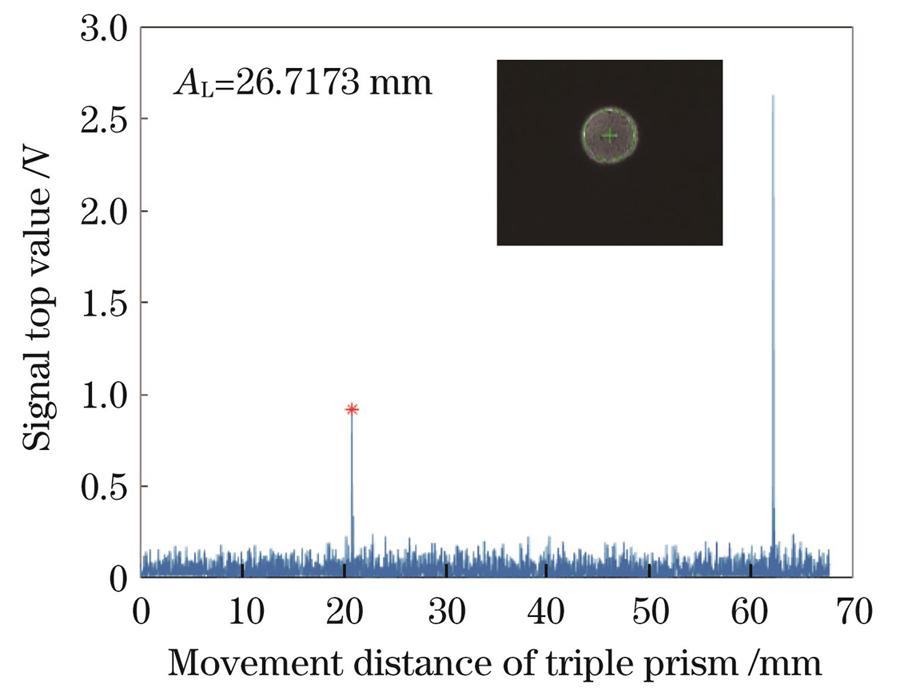

Five volunteers were recruited inside the laboratory, and the operator measured the subject’s left eye using the system experimental prototype and randomly showed the result of the eye axis length, radius of curvature, anterior chamber depth, and images of the measured human eye on the wavefront aberration sensor (Fig.3, Fig.4, Fig.5, Fig.6). The quality of the acquired images was good. The experimental prototype was used to measure the standard eye model with different diopters. The results of the single-sample t-test showed that the significance of the P value was greater than 0.05 (Table 1), and there was no difference between the diopter detection value of the experimental prototype and the standard value of the standard eye model, indicating that the experimental prototype could ensure measurement accuracy. From the values of Sw and TRT, it can be deduced that both the ocular biological parameters and diopter measurements have high repeatability. The CoV of eye biological parameters was less than 3%, the variation in the axial length and corneal curvature was smaller (CoV is less than 0.256%), and the ICC was higher than 0.6, reflecting high consistency (Table 2). The Bland-Altman analysis of the eye axis length, radius of curvature, and anterior chamber depth measured by the experimental prototype and IOL Master 500 showed no significant difference (P>0.05); the difference range was very small, and the 95% consistency limit was -0.045-0.056 mm, -0.037-0.056 mm, -0.534-0.355 mm, respectively, and all the measurement results were within the consistency interval (Table 3).

2.2 眼轴长度测量光路设计

本团队设计的眼轴长度测量系统[21](New AL)是基于双光路外差干涉原理搭建的泰曼-格林干涉系统,该系统主要由近红外超辐射发光二极管S3(中心波长为790 nm,带宽为30 nm,偏振度为1000∶1)、准直镜L14、分光棱镜BS(分束比为50∶50)、角锥棱镜P1和P2、光电探测器D和数据采集卡(DAQ)组成。干涉信号经光电探测器转换为电信号后再由前置放大器Pre放大,之后被数据采集卡采集并被输入计算机,对数据进行分析即可得到眼轴长度。

在实验室内招募了5名志愿者,因为都是年轻人群,因此没有设置排除条件。虽然这5名志愿者的眼球有不同的屈光状态,但基本都是健康的。采用本团队搭建的实验样机对5位受试者的左眼进行测量,采集的典型结果如

结合光外差干涉和波像差分析等技术,设计了眼屈光度与生物参数测量的一体化系统,实现了眼轴长度、角膜曲率、前房深度和屈光度等参数的测量。一体化实现过程的难点主要在于眼轴长度的测量。测量眼轴长度需要获取角膜表面的干涉峰值信号与眼底视网膜干涉的峰值信号,而眼底视网膜信号较弱,干涉信号的信噪比不高。为了提高信噪比,在两方面进行了改进:一是提高电机速度的控制精度,降低信号频率范围,保证信号频率稳定,提高信号的提取能力;二是采用数字信号处理的方式,在不损失信号强度的前提下大大提高了信噪比。未来,也可以对眼轴信号进行多次测量,利用信号处理手段来提高信号的提取能力,进一步提高检出率。需要说明的是,本研究纳入的受试者均为年轻学生,不包括儿童和老年人,因此在评估不同健康水平和不同年龄段人群的眼屈光度时存在一定的局限性。从笔者获取的人眼的测量数据可以看出,所搭建的系统具有出色的重复性,尤其是在眼轴长度和角膜曲率测量方面具有很高的稳定性。虽然该系统在测量前房深度和屈光度方面仍然存在误差,但随着数据量的不断增加,可以通过一些技术手段来解决,比如对前房深度的提取算法进行优化。屈光度测量准确性的提高可以从以下两方面进行: